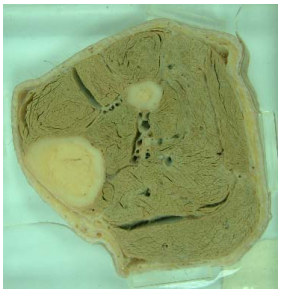

11. 依附圖骨骼及肌肉的特徵判斷,應是下列何部位的橫切面?

(A)大腿 (B)小腿 (C)上臂 (D)前臂